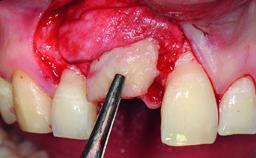

Bone Augmentation Horizontal|Simultaneous|Staged

Augmentation Materials Autogenous chips|Xenogenous|Membrane

Bone Volume Deficient horizontally, requiring prior grafting